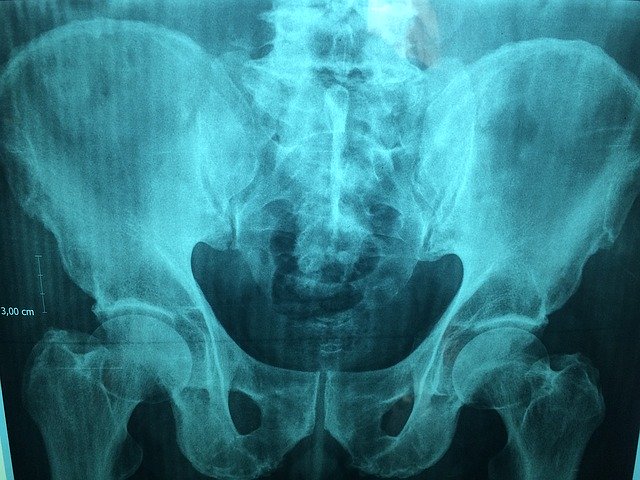

痛みが出たら無理にしないと言われていたが、どんどん痛みで出来なくなる。ぎっくり腰がキッカケの腰だけど、実は【骨盤のゆがみ・反り腰】が重度だった。骨盤のゆがみは昔から言われていたので理解できるのだけど、反り腰って言われてビックリしてしまった。もう産後のボロボロの体で抱っこして、ケアしなかった結果だと気付いて泣いた。

実際、長年困っていた右腕のピリピリが体調悪い時以外は無くなった。ちなみに骨盤の仙骨には多くの神経が通っており、この中に自律神経も含まれている。メンタルが落ちると、神経が緊張状態になり筋肉が強張るという状態が続くと骨盤がゆがむらしい。

脳と仙骨を背骨が繋げているのだが、骨盤がゆがむと神経が圧迫されて自律神経も乱れる。なので体が強張ってしまった時に自律神経が乱れているでしょ?と昔苦手になった整骨院で言われたのは、骨盤が歪んでるから言ったのではないか?と言われた。あながち間違いではないと言われて、過去の思い出も浄化された気分。

さっき言った通り骨盤のところに自律神経があるので、骨盤のゆがみを整えることで自律神経が正常に動き交感神経から副交感神経への切り替えが上手くいき眠りやすくなります。不眠症の方は、一度骨盤のゆがみを気にすると良いかもしれない。